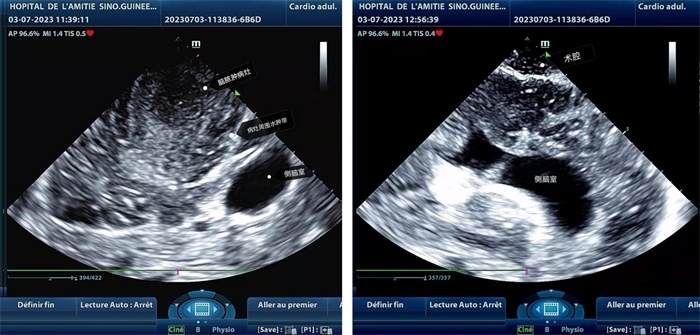

手術(shù)中,張國濱在超聲科顧秀娟的幫助下,運用顱腦術(shù)中超聲技術(shù),通過將一次性保護套的超聲探頭置于腦組織表面,實時觀察病變的位置和形態(tài),進一步確認(rèn)最佳手術(shù)路徑。術(shù)中超聲顯示,病變位于左額頂葉,大小約為4x4x3cm,邊界清晰,呈囊實性,周邊腦組織水腫明顯。最終,病灶順利切除,診斷為腦膿腫,并通過超聲檢測確認(rèn)術(shù)腔無病變殘留、無出血,為患者術(shù)后恢復(fù)提供了良好的保障。

左圖顯示術(shù)中超聲見囊實性病變,大小約為4x4x3cm,病灶周圍腦組織水腫明顯;右圖為病灶切除后,術(shù)中超聲示術(shù)腔無病變殘留

左圖顯示術(shù)中超聲見囊實性病變,大小約為4x4x3cm,病灶周圍腦組織水腫明顯;右圖為病灶切除后,術(shù)中超聲示術(shù)腔無病變殘留。中國第二十九批援幾內(nèi)亞醫(yī)療隊供圖